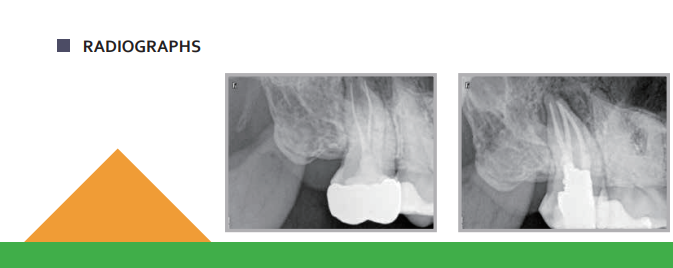

Dia-ProSeal- root canal sealing material

Dia-ProSeal Root Canal Sealer is a two-component epoxy resin-based system